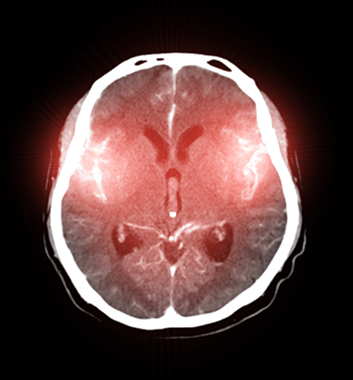

뇌의 문제로 어지럼증이 생기는 경우입니다. 뇌혈관의 문제가 있거나 소뇌에 문제가 있을 때 발생할 수 있습니다. 이런 경우는 뇌 검사를 통한 빠른 치료가 필수적입니다.

중풍이라고 부르는 뇌경색이나 뇌출혈로 인한 어지러움